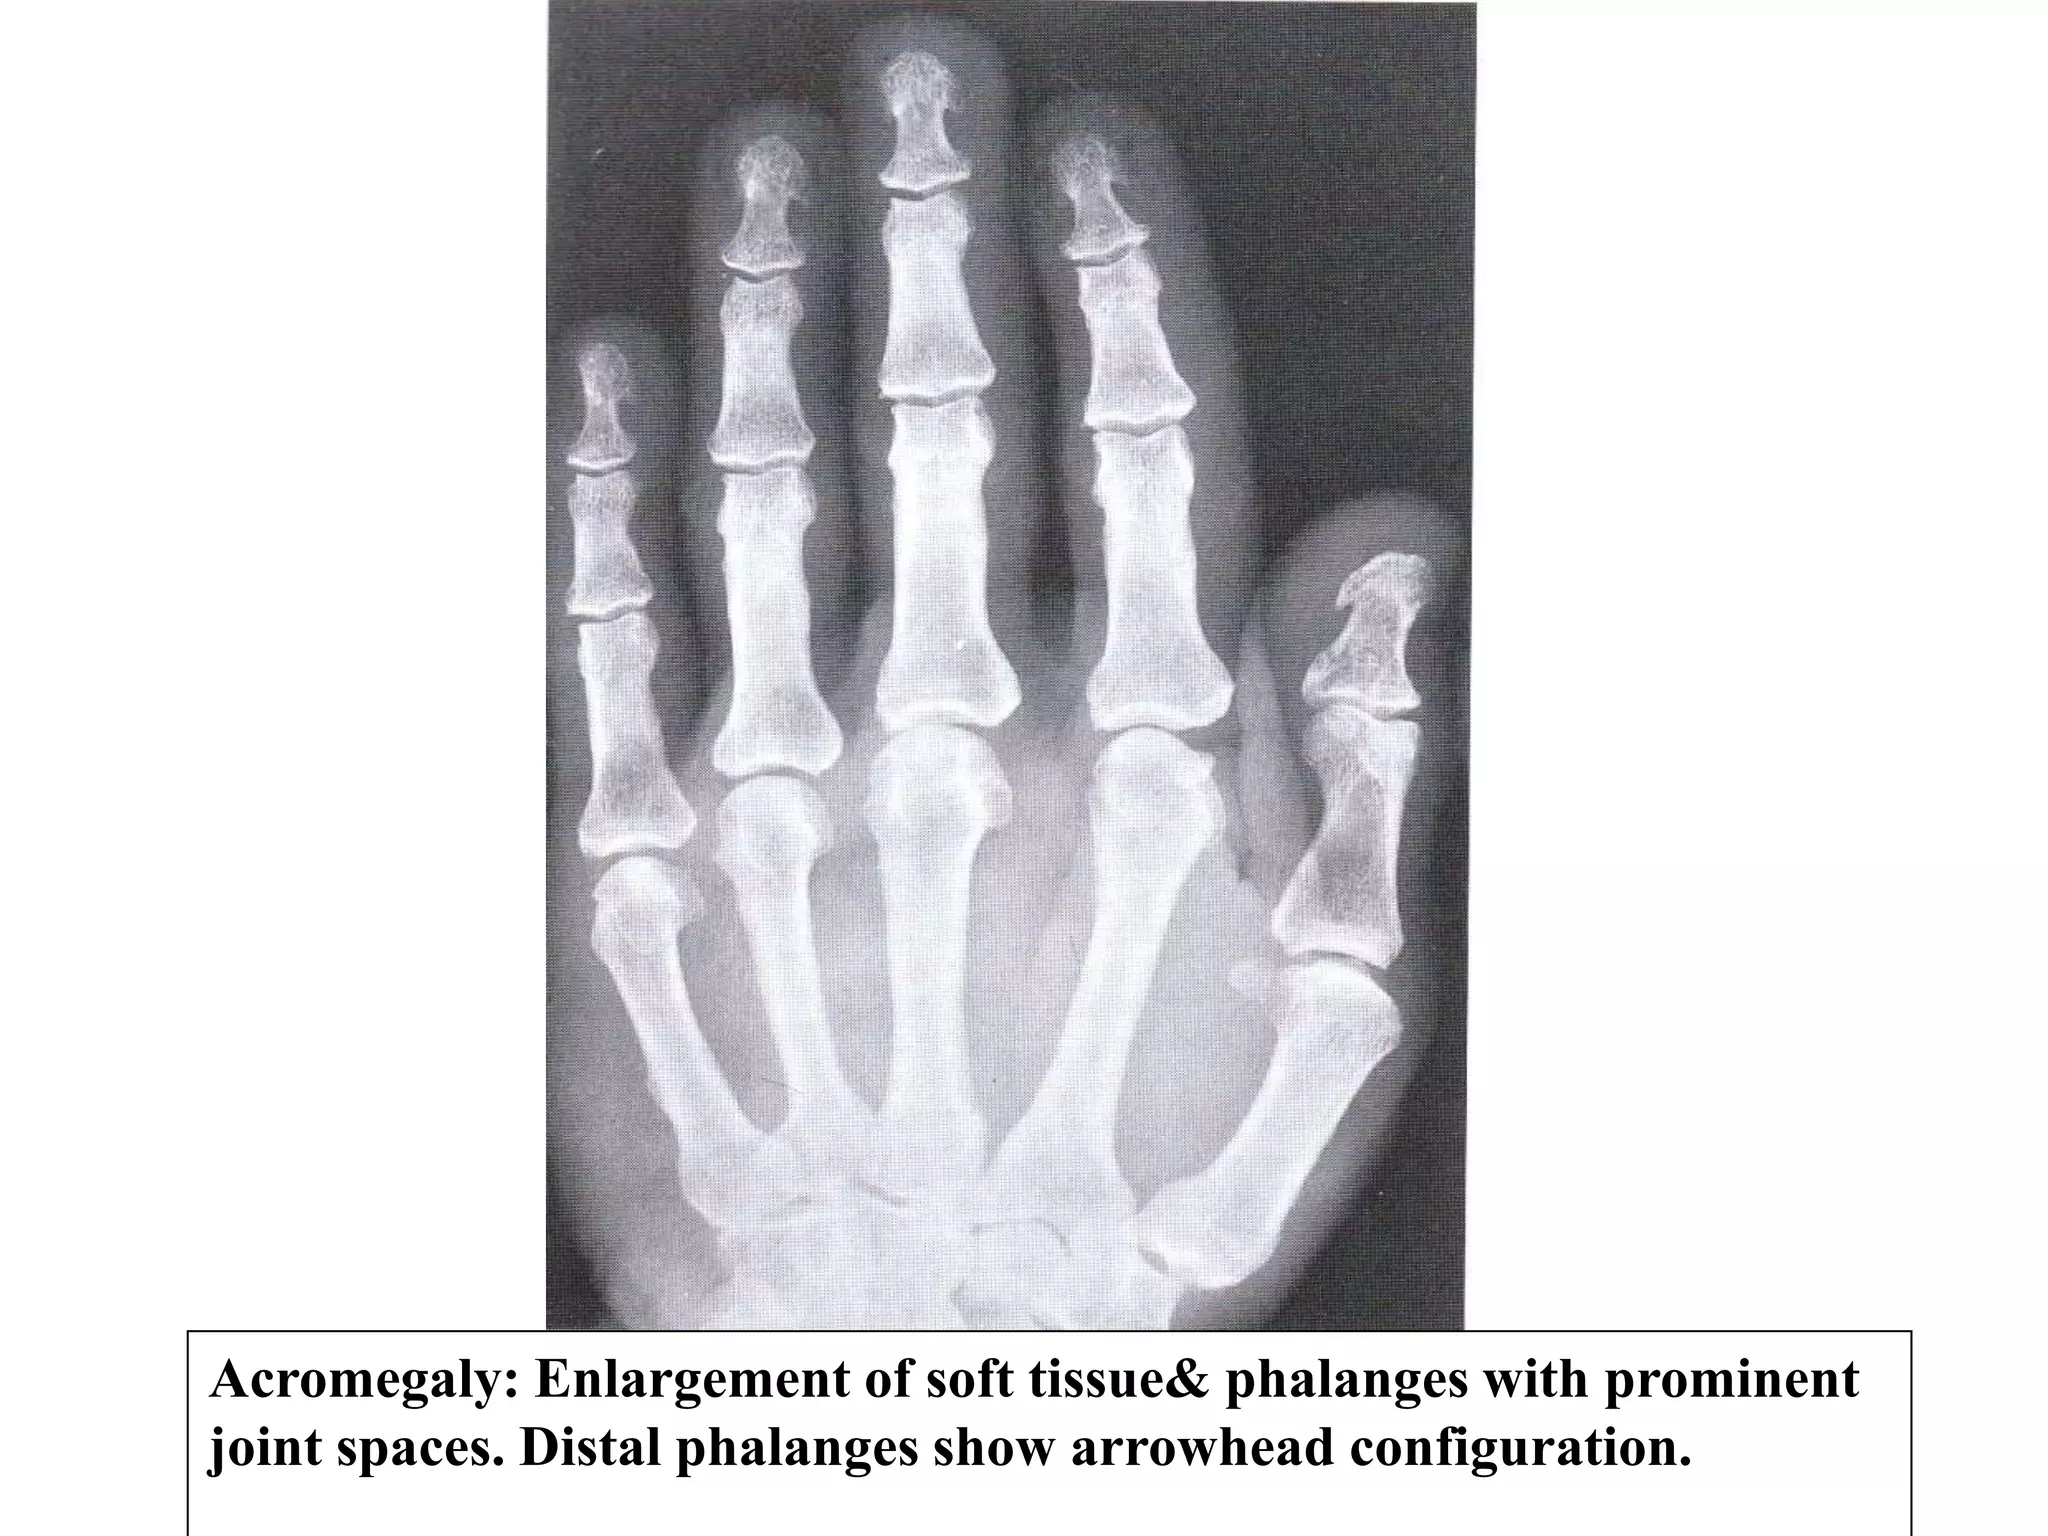

Appendicular Skeleton:

• Hands show characteristics enlargement of bones &

soft tissue with spade like appearance of terminal tufts

or arrow head distal phalanges.

• Widening of the joint spaces (overgrowth of articular

cartilage).

Acromegaly: Enlargement of soft tissue& phalanges with prominent

joint spaces. Distal phalanges show arrowhead configuration.